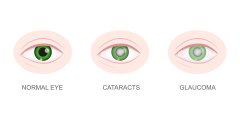

青光眼是世界第二大致盲性眼病,可導致單眼失明,也可導致雙眼失明,而且是不可逆轉(zhuǎn)的。而很多人不知道的是,青光眼在任何年齡段均有幾率發(fā)病,上至耄耋老人小至襁褓中的嬰兒都可能罹患此病。特別是用眼強度較大的年輕人,發(fā)病率有逐年攀升的趨勢。

青光眼初期的癥狀一般都不是特別明顯的,如果大家懷疑自己出現(xiàn)了以下青光眼的癥狀的話,一定要到醫(yī)院進一個詳細的眼部檢查,確診是否患上了青光眼的。

1、視野變窄,視力下降